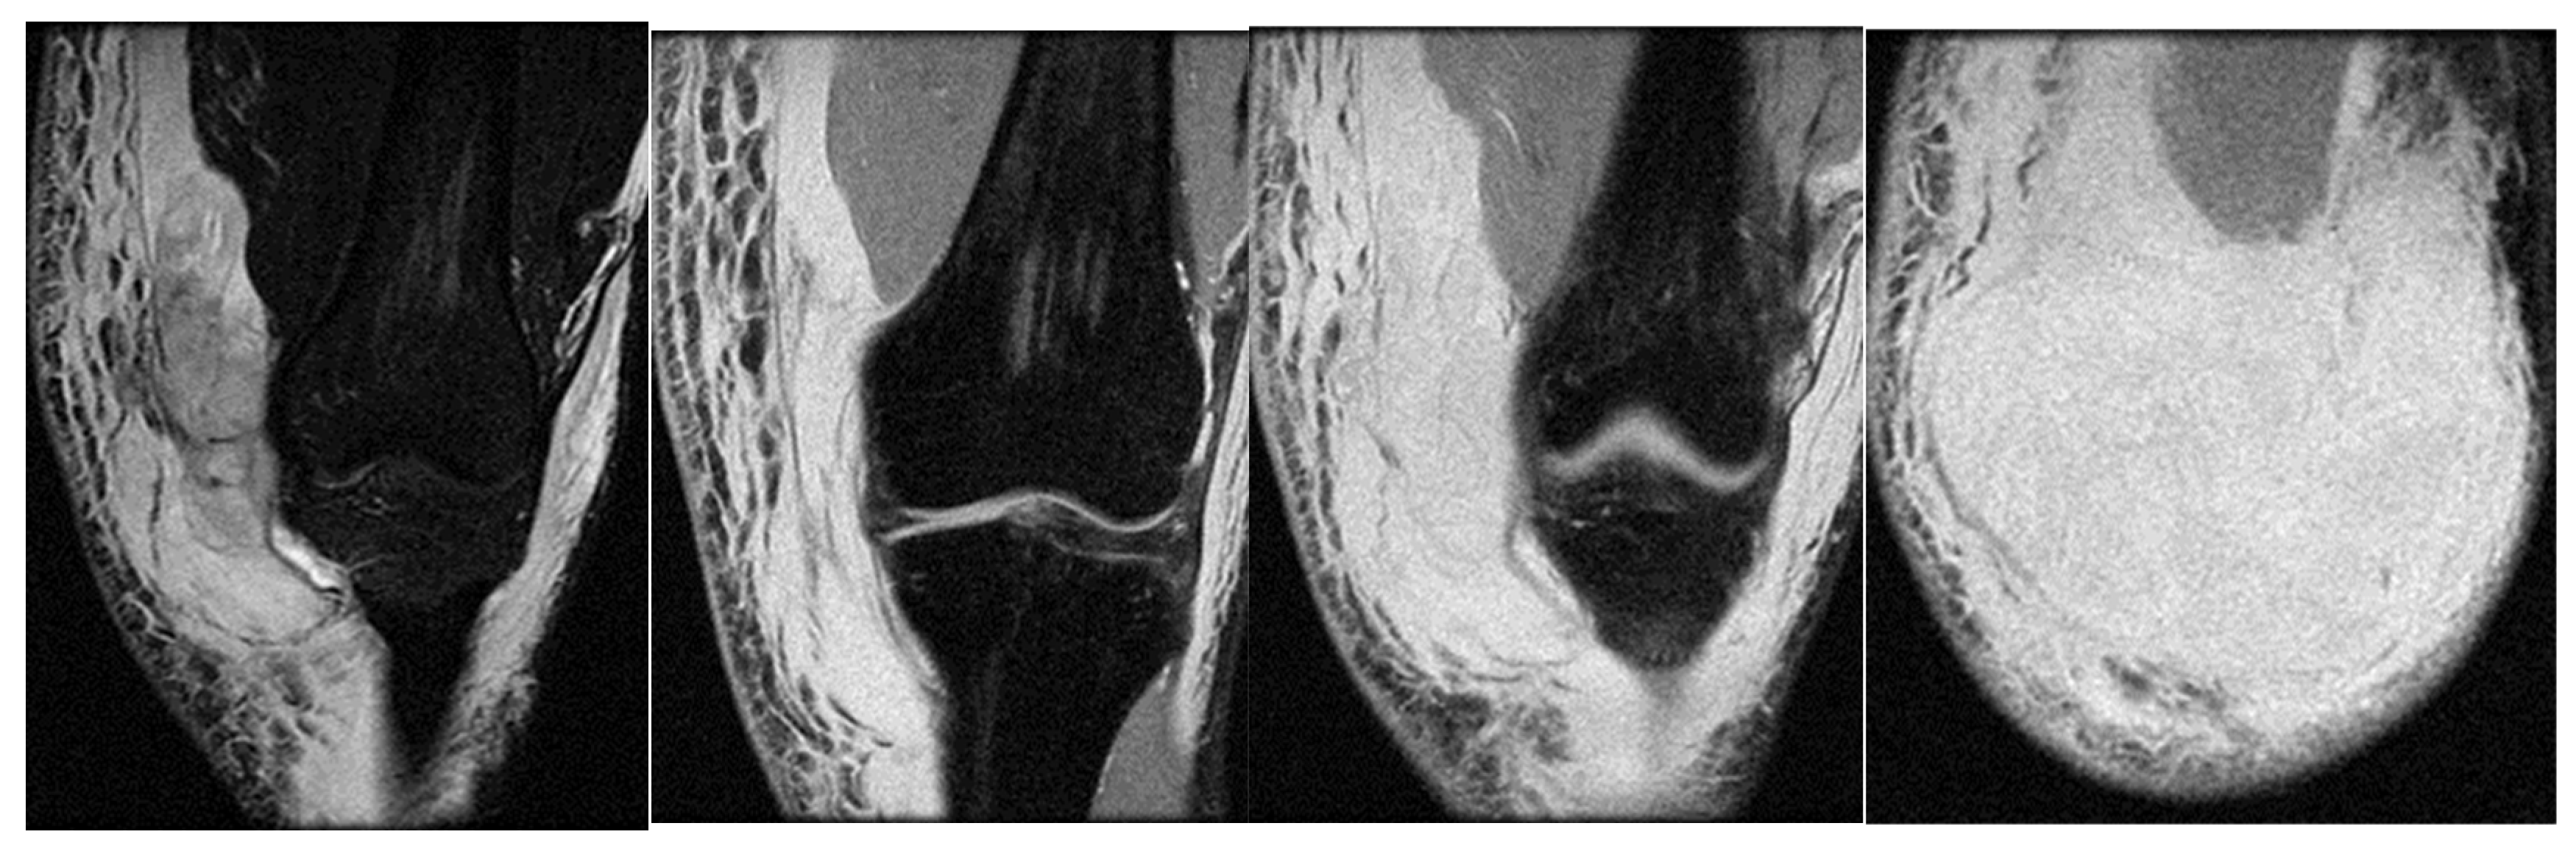

3.1. Case 1: Vastus Lateralis Tear with Prepatellar Hematoma

Right back, 22 years old, national-team player from a rural area, professional first-league athlete, 198 cm, 110 kg. In the initial case, the right back sustained injuries to the knee and the distal portion of the left thigh during a training session, attributed to a lateral concussion and the “opening” of the internal compartment. The clinical examination revealed pain, swelling, edema, a bubble knee, relative functional impairment, and restricted active and passive movement of the left knee. A sprain of the left knee was suspected, with potential damage to the meniscus, cruciate ligaments, and collateral ligaments. Although the MRI did not indicate any damage to the intra-articular structures, it did reveal a substantial prepatellar extraarticular hematoma, resulting from a muscle tear in the vastus lateralis muscle, along with significant edema of the soft tissue. The extraarticular edema is evident in the non-homogeneous Ts and STIR hyperintense, accompanied by T1 hypo- and hyperintense. Post-traumatic edema of the adjacent soft tissue is depicted in STIR as an altered diffused hyperintense (Figure 1, Figure 2 and Figure 3).

Sagittal T2 acquisition.

Knee MRI: axial T2 acquisition.

Knee MRI: coronal stir acquisition.